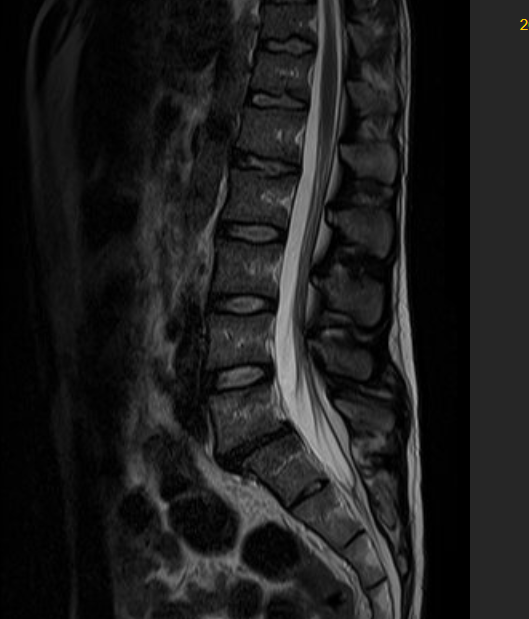

DIAGNOSI:

SPONDILOLISTESI LOMBARE DI II GRADO L5-S1

Risonanza magnetica pre-operatoria

Intervento chirurgico eseguito:

STABILIZZAZIONE PERCUTANEA SEMPLICE

Radiografia lombare post operatoria